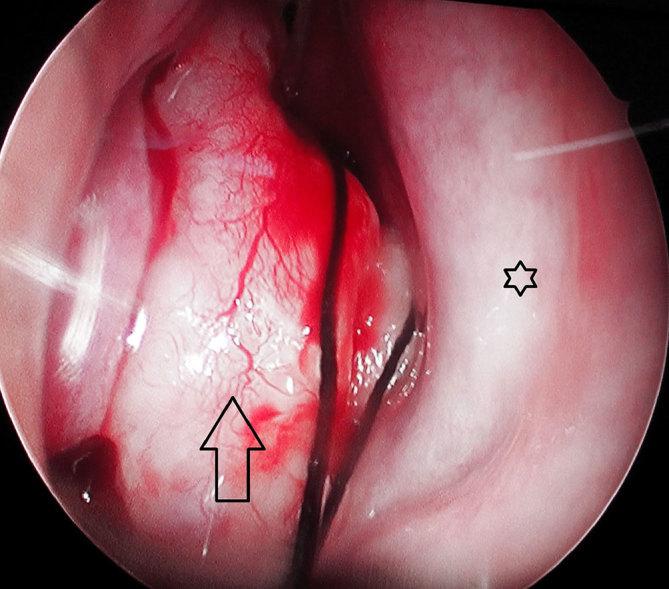

Two cases of fibrous dysplasia involving the middle nasal turbinate are presented. Fibrous dysplasia is a common benign fibro-osseous disease involving the flat bones, often affecting the bony structures of the skull and facial skeleton. Primary occurrence or secondary involvement of the nasal turbinate is not a common manifestation of the disease. Involvement of the inferior turbinate generally does not have specific management-related issues; however, involvement of the middle turbinate, especially the lateral lamella, can predispose to surgical morbidity during endoscopic surgical management. Clinical presentation, management and features of the disease on CT imaging are presented.